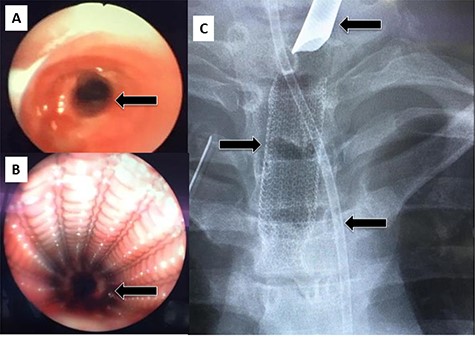

Case 1—bronchial injury

A 27-year-old male presented to the Trauma Room after a fall from a 3-meter height. Because of low Glasgow coma scale (GCS), hypoxia and diffuse subcutaneous emphysema, the patient was intubated, and bilateral chest tubes were inserted. After stabilization, a pan computed tomography (CT) scan was performed and revealed extensive subcutaneous emphysema of the neck and chest, as well as bilateral pulmonary contusion. The patient was admitted to the Trauma intensive care unit (ICU) for supportive treatment, where he continued to have hypoxia as well as a persistent right-sided pneumothorax on a repeated chest X-ray. Because a major airway injury was suspected, a bronchoscopy was performed, which revealed a full-thickness laceration in the region of the bronchus intermedius/right middle lobe bronchus. Due to persistent hypoxia, the ECMO team was consulted and the patient was started on Veno-Venous (VV) ECMO. With ECMO support, he was shifted to the operating theater (OT) for right anterolateral thoracotomy and repair of the bronchial defect. The surgery was uneventful, and the patient returned to the ICU in stable condition. He remained sedated, on lung-protective ventilation, as well as ECMO support. The patient underwent tracheostomy on Day 5 and was successfully removed from ECMO and decannulated on Day 16. He remained in the ICU for 25 days, after which he was transferred to the ward in stable condition. Follow-up flexible bronchoscopy showed an intact bronchial tree, with only a partial occlusion of the lumen. The patient was discharged home in stable condition with regular follow-up in the outpatient clinic.